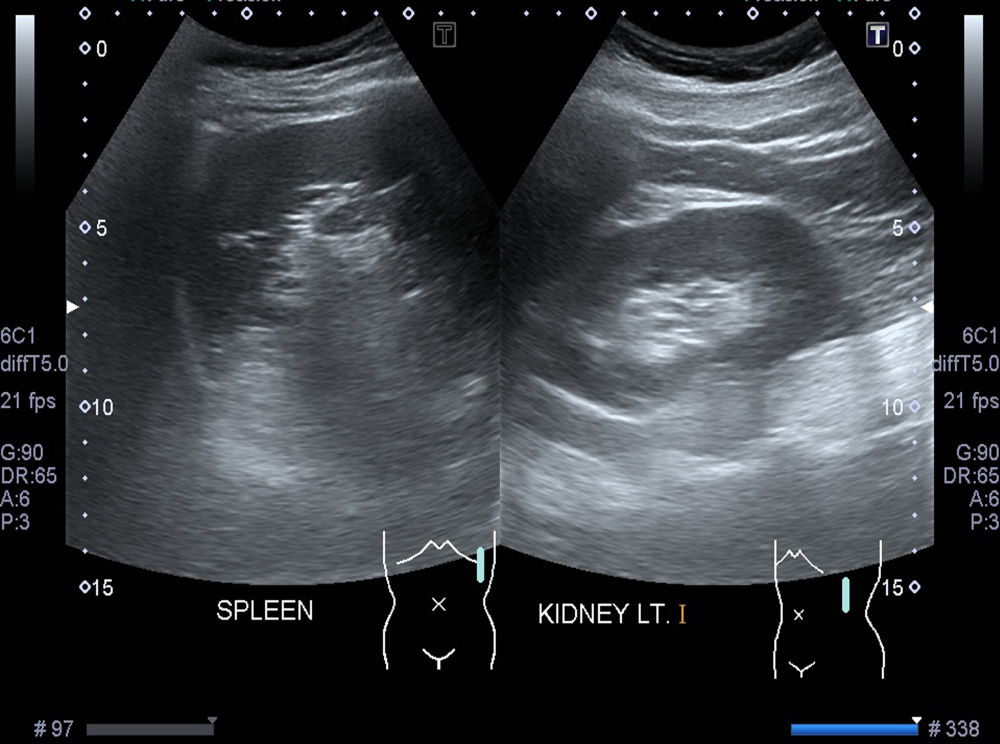

Фотогалерея

По окончании процедуры результат выдается практически сразу. В ходе расшифровки доктор анализирует снимки органа. Измеряет размеры. Определяет другие его особенности. Сравнивает с нормальными значениями. Врач отмечает присутствие и локализацию выявленных патологических процессов. Устанавливает их параметры, форму, протяженность, контуры, степень инвазии. Данные специалист переносит в протокол. Печатает самые информативные фотографии.

Норма размеров селезенки по УЗИ у взрослых:

- длина в промежутке от 8 до 14 сантиметров;

- ширина около 5–8 сантиметров;

- толщина – 3–5 сантиметров;

- вес у лиц женского пола примерно 152 грамма, у лиц мужского пола – 192–200 грамм;

- эхогенность органа средняя;

- структура однородная;

- патологические включения отсутствуют.